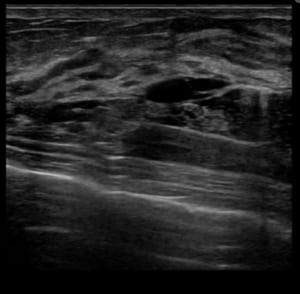

このエコーを解説しますと、